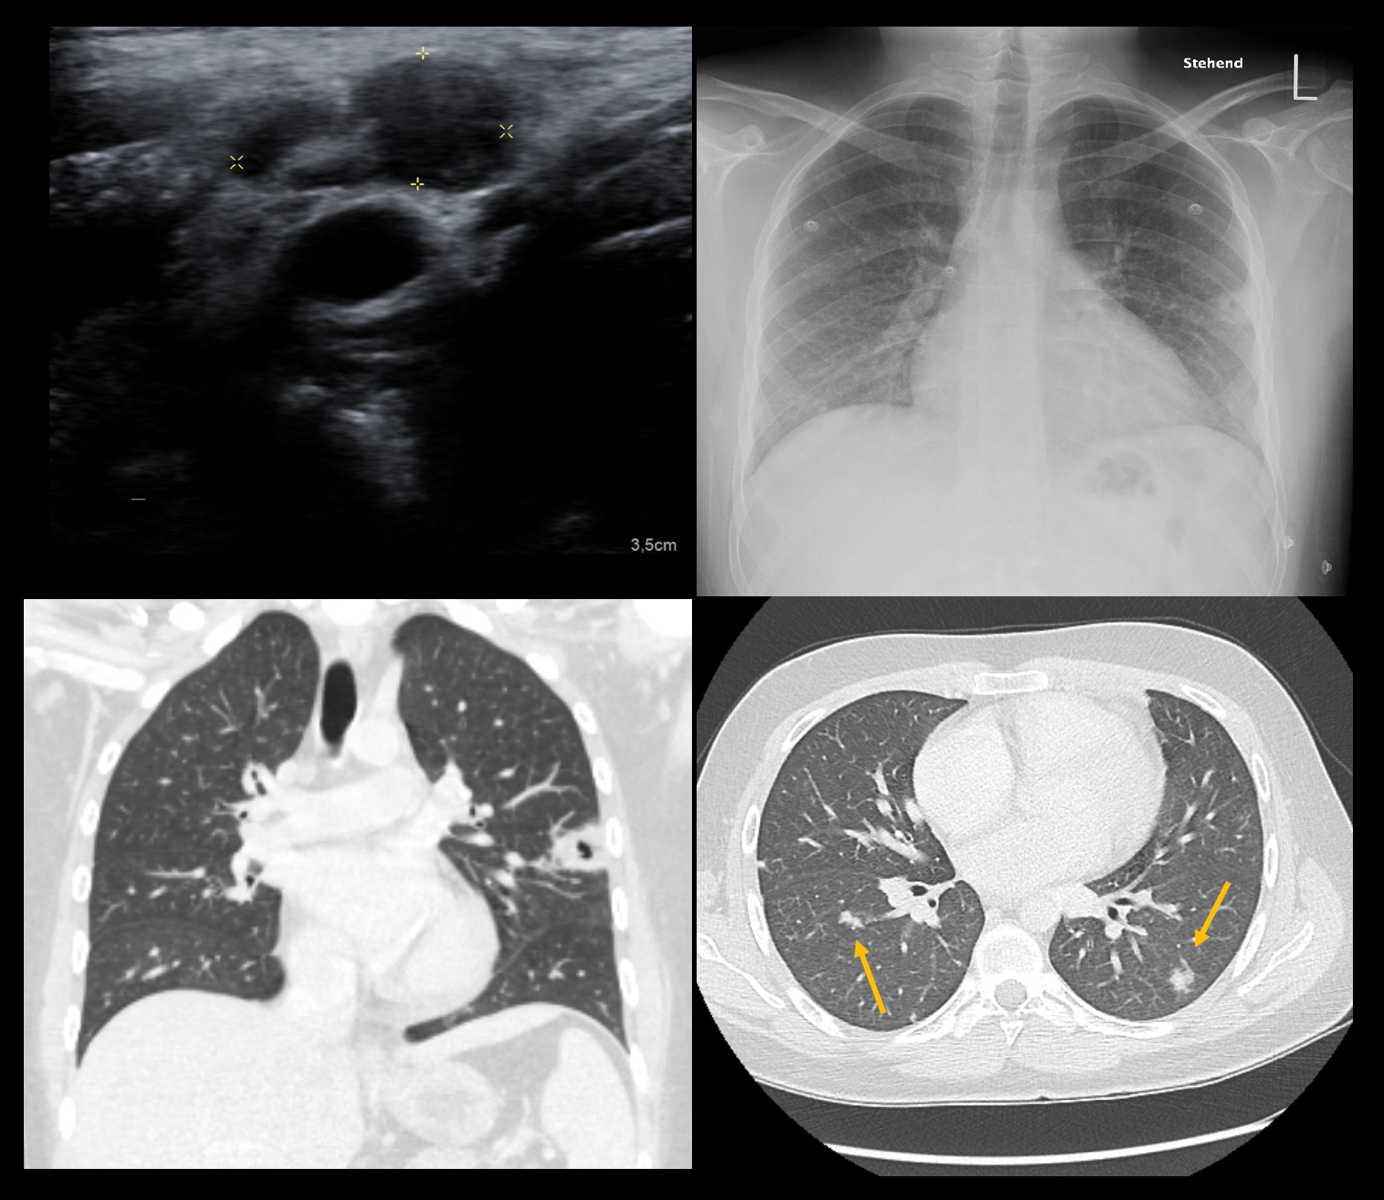

Il paziente è stato sottoposto ad una radiografia del torace per chiarire le origini della dispnea, ad una TC torace e ad un'ecografia del collo. Sono state effettuate anche delle emocolture.

Imaging: ecografia, radiografia e TC

La radiografia mostra una cavità nel lobo polmonare superiore sinistro, mentre la TC mostra altre lesioni nodulari polmonari cavitate diffuse in tutti i lobi polmonari. L'ecografia rivela una tromboflebite della vena giugulare interna di sinistra.